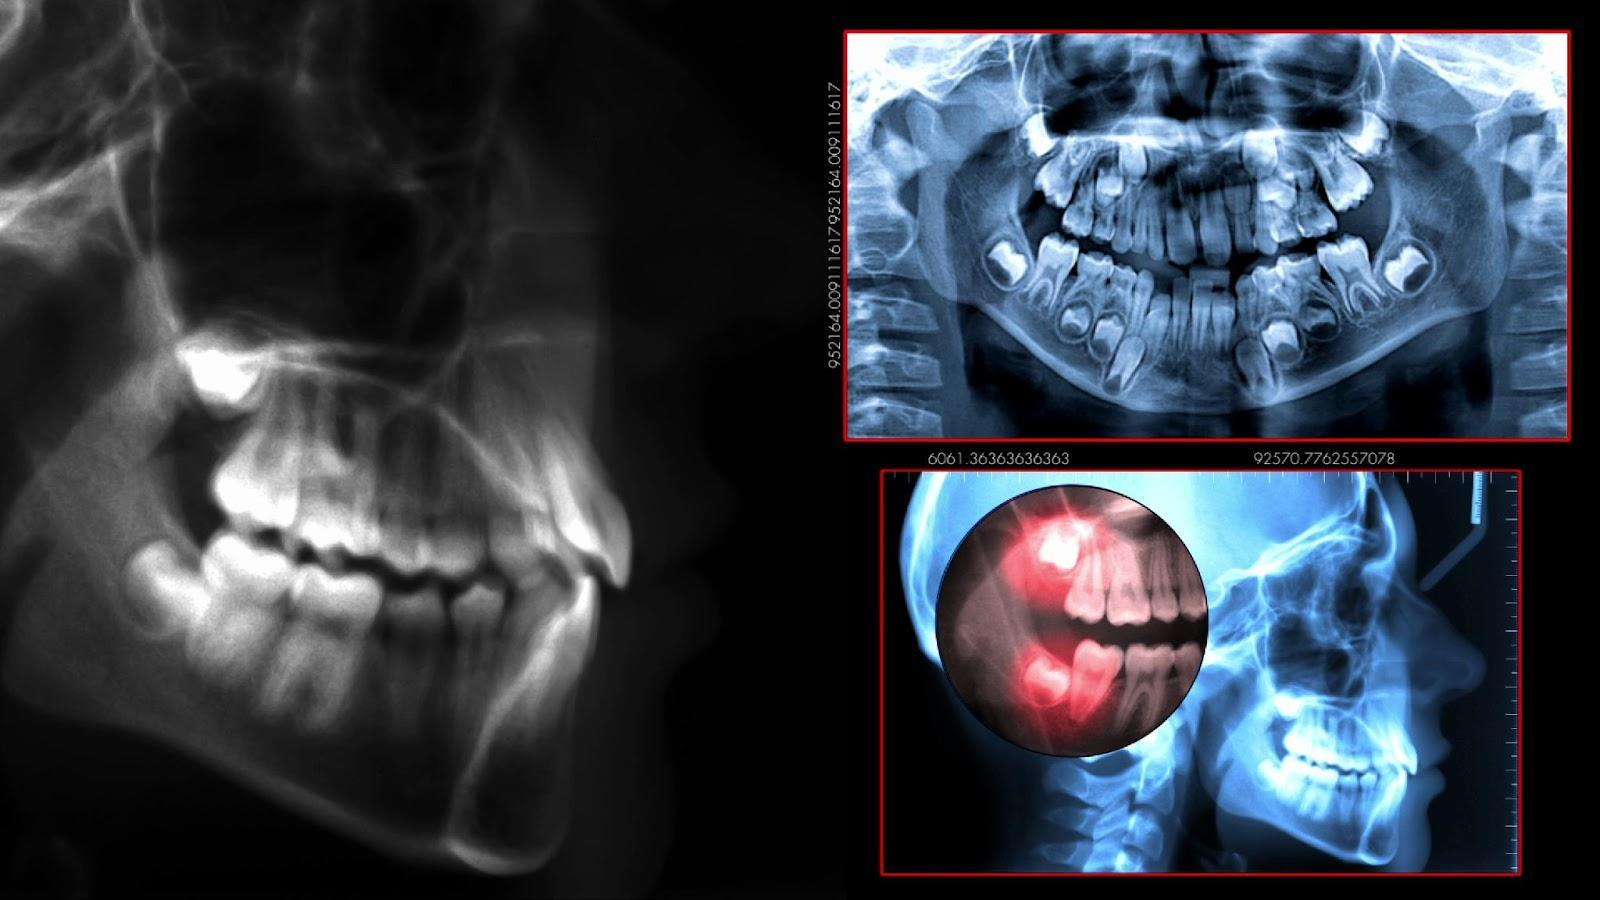

歯科用CTは、従来のレントゲンよりもはるかに高精度な三次元画像で、歯や顎の骨、神経、血管などの状態を詳しく確認できる検査機器です。

歯科用CTは歯や顎の状態を立体的に撮影し、より正確な診断と治療計画を立てるための検査機器です。

通常のレントゲンでは2Dでしか確認できない部分を、歯科用CTでは3D画像として表示できるため、歯や骨の内部構造、神経や血管の位置まで詳しく把握できます。